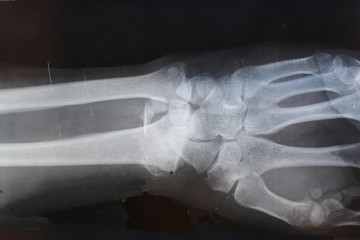

Биоклей испытали более чем в 150 клинических случаях. В одном из них пациент с переломом запястья избежал установки металлической пластины: после трехминутной процедуры и последующего трехмесячного наблюдения кость полностью восстановилась без осложнений.